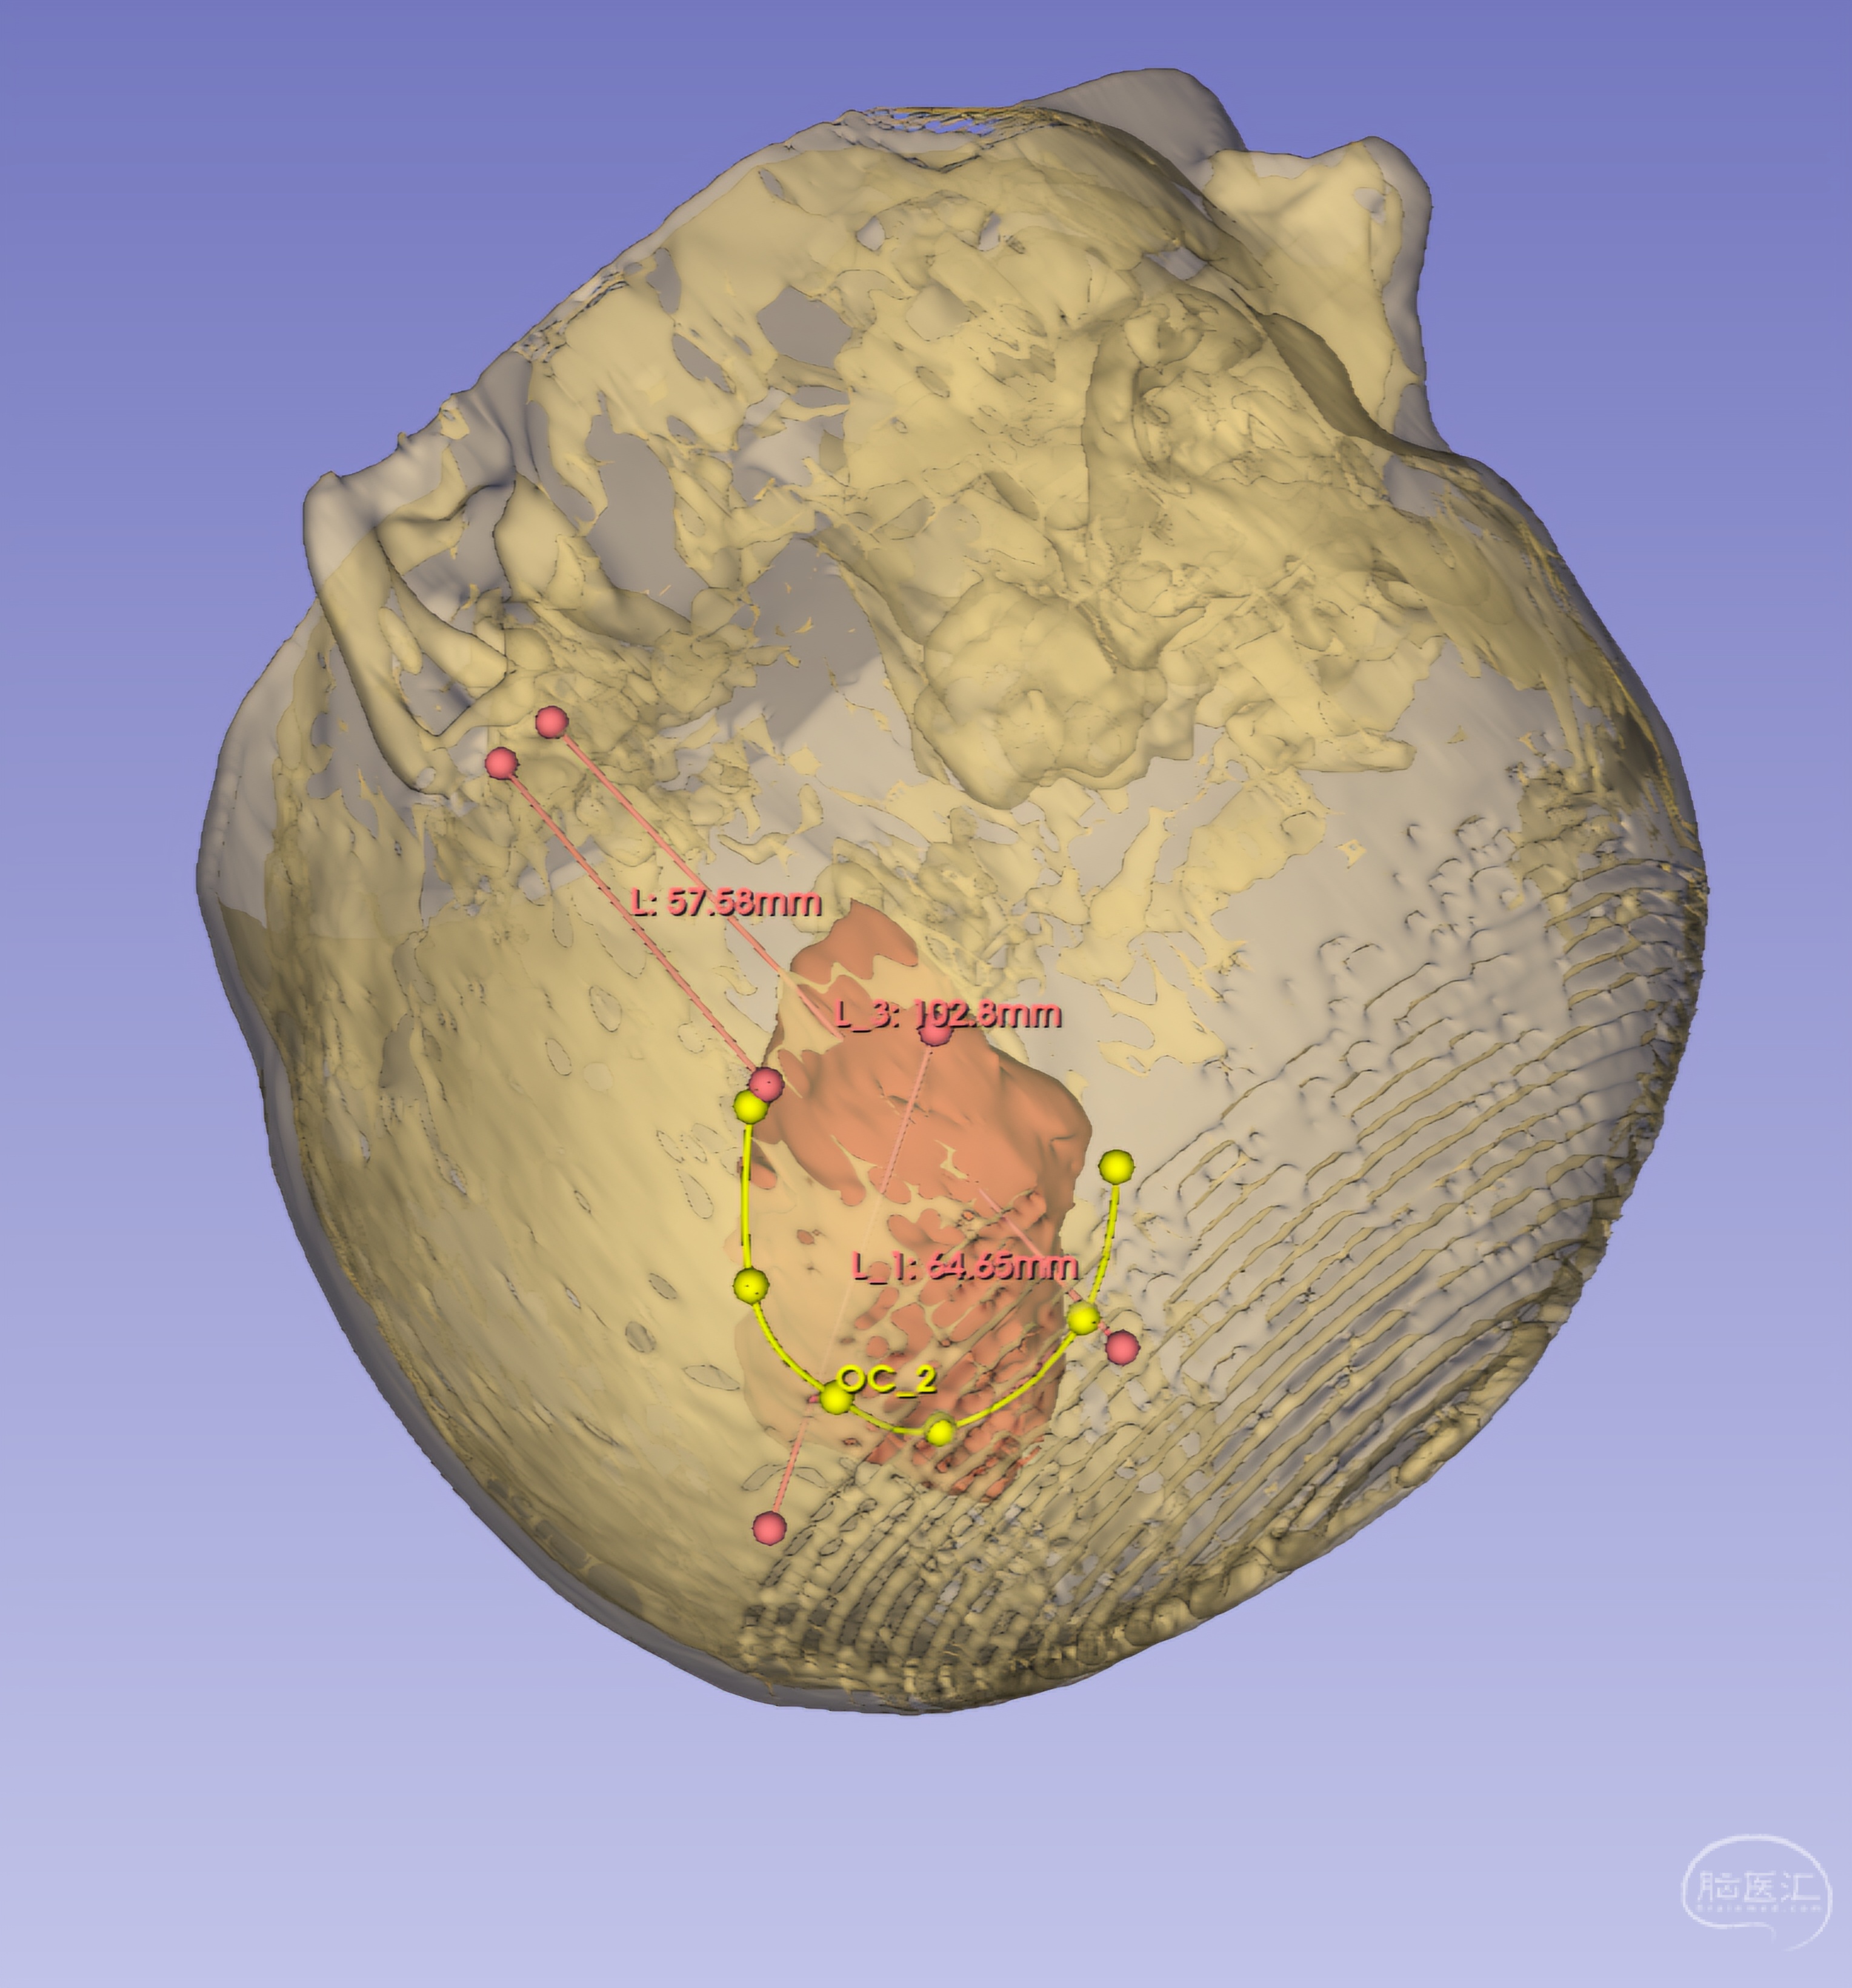

术前用3DSlicer重建了一下血肿位置,下界大概位于耳廓上方约6cm,上界位于耳廓上方约10cm

根据术前重建大致定位血肿上下界,再以前囟点后5cm(中央沟上端点)和耳前凹陷上5cm(中侧裂点)定位中央沟体表投影,即为血肿前界,以血肿为中心设计一小弧形切口

再用Sina投射软件做个血肿腔投影,位置大体一致